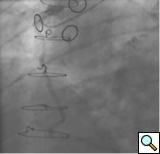

PCI of the vein and arterial grafts have unique challenges. For any PCI, guide support is very important for successful balloon and stent delivery. In a tortuous vein graft with a steep angle, advancement of a stent can be very difficult and challenging. Therefore, it is important to choose the best available catheter before starting PCI. Similar to the right coronary angiography, a JR4 guide catheter is most commonly used in this setting. However, Amplatz guide catheters for left vein grafts and multipurpose catheters for right vein grafts are better choices in certain anatomy. In Figure 8 and Figure 10 two examples of poor guide support in two vein graft interventions can be seen. Initially, a JR4 guide was used for PCI of the vein graft supplying the left anterior descending artery (LAD) without any success. However, after changing the guide to an Amplatz left 2 guide catheter, we achieved excellent support without any difficulty in advancing two stents (Figure 9). In Figure 10, difficulty is illustrated in engaging the vein graft ostium supplying the right coronary artery with a JR4 catheter. This vein graft has a very steep inferior take off from the aorta. After changing the guide to a multipurpose catheter, we were able to deliver three stents successfully without any difficulties (Figure 11). Similar challenges exist in the treatment of the left IMA or right IMA. These arterial grafts can be extremely tortuous making stent delivery very difficult. It may be necessary to use short length stents for a better deliverability or stents with lowest profile. Usually, similar to the native coronary intervention, a 6 French guide is appropriate for the routine use.

Similar to the native coronary, a 0.014 inch wire is usually used for balloon angioplasty or stenting. If the stent can not be advanced using a soft wire, the wire could be exchanged over the balloon to a stiffer wire or the second wire could be advanced and used as a body wire for a better support. If possible, filter wires or other protection devices should be used in all vein graft interventions [(Figure 2, see no-reflow chapter for details. Most commonly used work horse wires are balanced mid weight (BMW Boston Scientific), all track wire (ATW Cordis) or Prowater (Abbott Vascular)]. In the tortuous vessels, it may be necessary to exchange the wire over a balloon to a stiffer wire such as platinum plus or an iron man. Additional wire for support so called” body wire” can be utilized to improve stent delivery in tortuous vessels. Similar to the native coronary angioplasty, wire with stiffer or/and hydrophilic tips can be used for crossing a high-grade lesion such as PT choice, grand slam, PT2 wires, etc. However, these wires can easily enter a false lumen causing dissection or perforation. It is advised to exchange these wires with a softer tip wire once the lesion is crossed successfully to prevent distal vessel perforation.

One of the most common complication of PCI during vein graft interventions is the occurrence of “no-reflow.” After angioplasty or stenting of a vein graft, sudden cession of the distal flow could occur. This phenomenon thought to be secondary to distal embolization and platelet aggregation [2-4]. It can cause myocardial infarction, arrhythmias, hemodynamic collapse and death. It is usually treated with intra-coronary infusion of adenosine, calcium channel blockers, or nitroprusside [5-9]. After aggressive pharmacological treatment, it is usually reversible but it can be refractory causing severe myocardial damage and infarction. It usually occurs in old degenerative vein grafts or in thrombus containing lesions. However, based on the angiographic appearance, it is hard to predict which vessel is proned to this complication. There are few strategies developed in order to prevent this complication. Intra-venous glycoprotein IIb/IIIa inhibitors, which are very potent platelet aggregation inhibitors, despite success in the native coronary interventions have failed to decrease this complication in vein grafts PCI [10, 11]. On the other hand, distal filter devices have shown to significantly reduce the occurrence of this complication in vein grafts and should be routinely used if technically feasible [12-14]. A major limitation of distal filter devices is the absence of large distal vessels that can accommodate these devices and difficulty to advance such a bulky device across a high-grade lesion or across a tortuous vein graft. A recently approved proximal occlusion device has similar efficacy for the prevention of no-reflow in vein graft interventions [15]. By occluding the vein graft proximally during balloon angioplasty or stenting, flow can be stopped during stent expansion and atherosclerotic and thrombotic debris can be suctioned before the vein graft flow is restored preventing distal embolization. This technique requires lesions that are distal to the ostial vein graft and add substantial complexity and time to the procedure. Figure 2 shows the most commonly used protection devices for vein graft interventions.